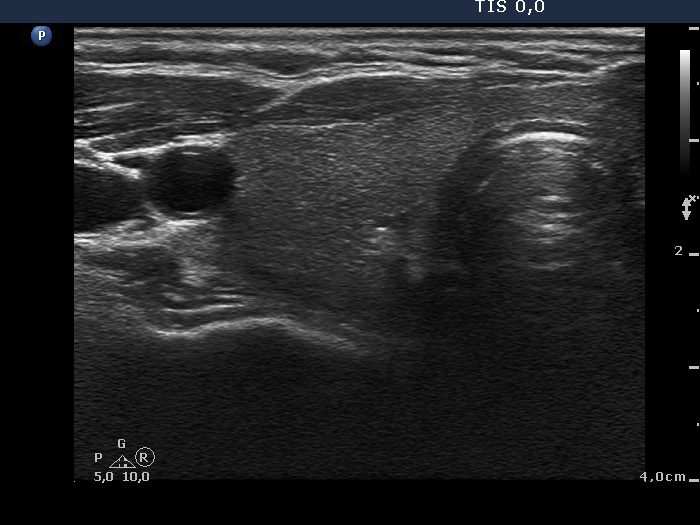

Ultrasonography. The right thyroid was moderately hypoechogenic without any circumscribed lesions. The left thyroid was removed. There were several enlarged lymph nodes in the right submandibular area. The largest one presented two discrete, more hypoechogenic intranodal lesions and a regular hilum.

Comment. This is an unusual case, the nodes (particularly those presented in the video) seem to be benign, reactive-type ones.